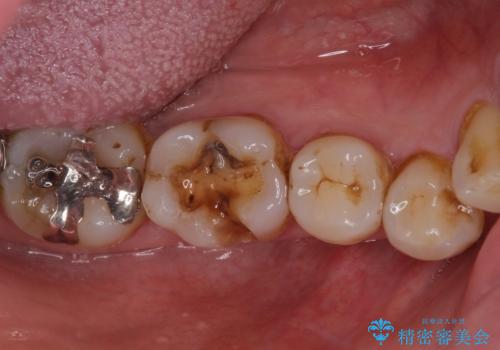

- 銀歯やインレーが外れたまま放置された奥歯の治療を希望して来院された患者様です。

咬合力が著しく強いため、欠損の多い歯はフルジルコニアクラウンへ、その他の虫歯はゴールドインレー(PGAインレー)にて修復することとしました。

来院時は全てセラミックでの治療を希望されていましたが、歯列や咬み合わせから咬合力による破損リスクが高いと判断されたため、ゴールドインレーを選択しました。